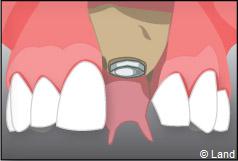

À l’issue de sa mise en place chirurgicale, une bague de cicatrisation en titane peut être directement vissée sur l’implant. Ainsi une seconde chirurgie ne sera pas nécessaire pour découvrir l’implant.

Exemple d’un implant unitaire pour remplacer une dent antérieure manquante.